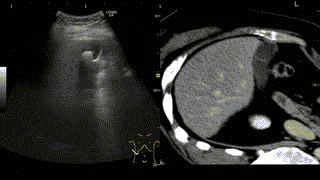

![]() |

☆写真の説明☆CT画像と超音波画像を同じ断面で比較しながら観察が可能です。 |